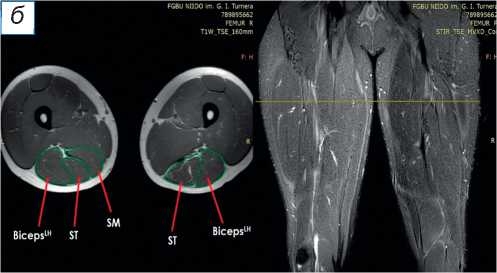

При поступлении в центр пациенту выполнены лучевые методы исследования нижних конечностей, в частности панорамная рентгенография и компьютерная томография (КТ) нижних конечностей; сравнительная МРТ мягких тканей правого и левого бедра (рис. 2). По данным рентгенографии и КТ-исследования, костно-суставной патологии не обнаружено. По результатам МРТ определены повреждения всех трёх мышц различной степени тяжести — SM, ST, BicepsLH (расположены в порядке убывания; см. рис. 2, а ). Длинная головка двуглавой и полусухожильная мышцы, вероятно, были оторваны у места крепления и не подверглись значительной ретракции; начало брюшка полуперепон-чатой мышцы визуализировано на границе верхней и средней трети бедра (ретракция 9 см).

Рис. 2. Сравнительная магнитно-резонансная томография мягких тканей правого и левого бедра (аксиальные и фронтальные срезы): а — изменение нормальной архитектоники полусухожильной, полуперепончатой и длинной головки двуглавой мышцы на уровне верхней трети правого бедра; б — на данном уровне не прослеживается мышечное брюшко полуперепончатой мышцы; в — на границе верхней и средней трети прослеживается мышечное брюшко полуперепончатой мышцы, спаянное с большой приводящей; определяется разница по форме и диаметру поперечника полусухожильной мышцы; г — на уровне средней трети отчётливо проявляются мышечное брюшко полусухожильной мышцы, несоответствие поперечного диаметра полуперепончатой и полусухожильной мышц с контралатеральной стороной, гипертрофия короткой и длинной головки бицепса; д — аналогичная картина и на границе средней и нижней трети. ST ( m. semitendinosus ) — полусухожильная мышца; SM ( m. semimembranosus ) — полуперепончатая мышца; BicepsLH ( m. biceps femoris ) — длинная головка двуглавой мышцы.